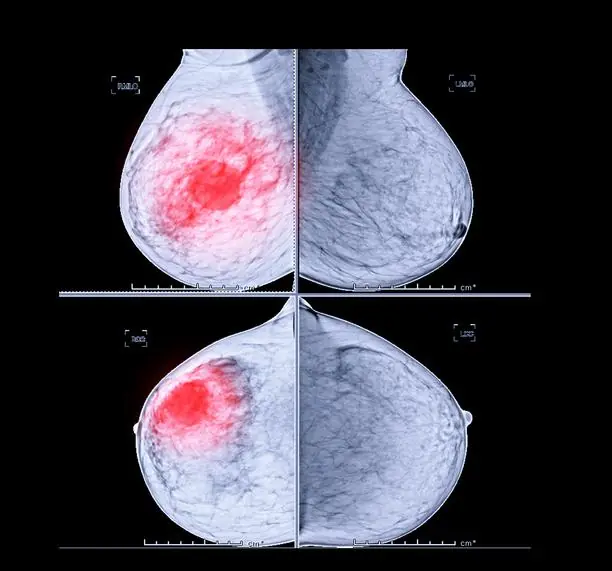

En la mamografía 2D, las estructuras anatómicas se superponen en una única imagen, lo cual puede ocultar lesiones pequeñas o simular hallazgos patológicos. La tomosíntesis, al ofrecer cortes secuenciales, permite evaluar el tejido capa por capa. Esta visualización tridimensional proporciona un mayor contexto anatómico y facilita una diferenciación más clara entre tejido normal y alteraciones sospechosas.

Uno de los principales desafíos de la mamografía 2D es la superposición de tejido glandular, especialmente en pacientes con mamas densas, lo que puede enmascarar lesiones y dificultar la interpretación. La tomosíntesis disminuye considerablemente este efecto, ya que separa las estructuras superpuestas en cortes independientes, revelando anomalías que de otro modo podrían pasar desapercibidas.

Gracias a su resolución volumétrica, la tomosíntesis permite detectar con mayor facilidad distorsiones arquitectónicas, masas pequeñas o lesiones de bajo contraste que la mamografía 2D puede no identificar. Estudios han demostrado que esta tecnología mejora la detección del cáncer invasivo sin aumentar significativamente los falsos positivos.

Mientras que la mamografía 2D puede ser suficiente en mamas con predominio de tejido graso, su rendimiento disminuye en pacientes con mamas densas. En estos casos, la tomosíntesis mejora significativamente la sensibilidad y especificidad diagnóstica, al ofrecer una evaluación más precisa del tejido mamario.